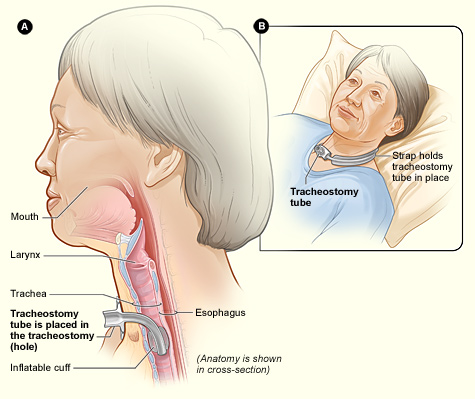

- Invasive Mechanical Ventilation – here a tracheostomy (insertion of a tube into the trachea from outside) is performed. It is only applied when the rest of the measures have failed (i.e., CPAP or NIV fails; deteriorating blood gases despite focused medical treatments) or conditions such as, clinical deterioration, sever respiratory acidosis or muscle fatigue. There are very high risks and complications of invasive mechanical ventilation and therefore it is only commenced in special cases and alway by a intensivist/specialist.

vocal cords:

1- Thyroid cartilage

2- Ring corpel

3- Tracheal cartilage

4- Balloon cuff